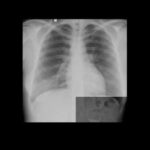

o paciente apresenta uma clavícula desviada para a direita, o que pode indicar um desvio causado por uma rotação do paciente. É importante considerar o contexto do paciente, como histórico de câncer de pulmão, que pode justificar uma atelectasia por obstrução brônquica. No entanto, se não houver justificativa para um desvio traqueal central, é possível que seja um artefato devido à rotação do paciente. É essencial pensar no porquê de cada observação e raciocinar antes de escrever um laudo.

Além disso, é mencionada a presença de uma fissura horizontal mais evidente que o normal, o que pode ser um indício de atelectasia. Também é observado um índice cardiotorácico aumentado e um coração que não cabe nos dois hemitórax, sugerindo congestão. O alongamento da aorta também é identificado, o que é mais comum em idosos. O duplo contorno e o sinal da Bailarina no coração indicam aumento do átrio esquerdo.

Outra observação é a presença de uma massa na região do diafragma, mas é importante saber que isso pode ser uma tração da fáscia diafragmática e não necessariamente um tumor. Essa é uma das armadilhas da radiologia, pois uma pessoa sem experiência pode confundir a tração com uma lesão maligna.

Por fim, é mencionada a presença de uma variação do normal, chamada de “irmãozinho”, na região diafragmática direita, que é uma proeminência de contorno normal. Essa ocorrência é mais comum à direita.